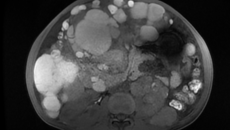

“药到病除”是每一位患者就医时的愿望,但有时遇到的却是“无药可医”的状况,这在面对癌症时尤为常见。何女士便是这样一位“病入膏肓”的癌症患者,十年间对疾病一直“放任自流”,直到不得已才选择住院治疗。 腹痛腹胀就诊,一查满腹肿瘤 2022年末,51岁的肾癌患者何女士因“腹胀、腹痛、体力低下、双下肢水肿”来到广西国际壮医医院肿瘤科就诊。受疾病影响,她卧床已有数月,身形消瘦,生活无法自理,更别提外出工作。 经身...08.072023